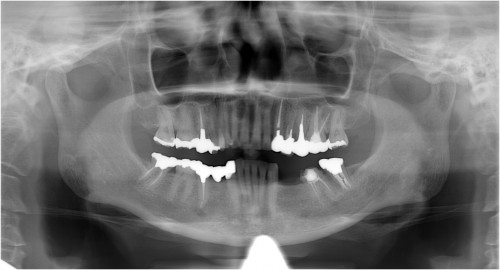

術前

左下5部 乳歯晩期残存

抜歯後

インプラント埋入直前

インプラント埋入直後

埋入後約3ヶ月

オペ時のISQ値

土台装着

被せ物装着

被せ物装着後